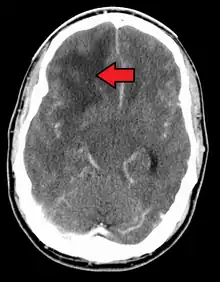

When viewed with MRI, glioblastomas often appear as ring-enhancing lesions. The appearance is not specific, however, as other lesions such as abscess, metastasis, tumefactive multiple sclerosis, and other entities may have a similar appearance.[63] Definitive diagnosis of a suspected GBM on CT or MRI requires a stereotactic biopsy or a craniotomy with tumor resection and pathologic confirmation. Because the tumor grade is based upon the most malignant portion of the tumor, biopsy or subtotal tumor resection can result in undergrading of the lesion. Imaging of tumor blood flow using perfusion MRI and measuring tumor metabolite concentration with MR spectroscopy may add diagnostic value to standard MRI in select cases by showing increased relative cerebral blood volume and increased choline peak, respectively, but pathology remains the gold standard for diagnosis and molecular characterization.

Distinguishing glioblastoma from high-grade astrocytoma is important. These tumors occur spontaneously (de novo) and have not progressed from a lower-grade glioma, as in high-grade astrocytomas[6] Glioblastomas have a worse prognosis and different tumor biology, and may have a different response to therapy, which makes this a critical evaluation to determine patient prognosis and therapy.[47][64] Astrocytomas carry a mutation in IDH1 or IDH2, whereas this mutation is not present in glioblastoma. Thus, IDH1 and IDH2 mutations are a useful tool to distinguish glioblastomas from astrocytomas, since histopathologically they are similar and the distinction without molecular biomarkers is unreliable.[48] IDH-wildtype glioblastomas usually have lower OLIG2 expression compared with IDH-mutant lower grade astrocytomas.[65] In patients aged over 55 years with a histologically typical glioblastoma, without a pre-existing lower grade glioma, with a non-midline tumor location and with retained nuclear ATRX expression, immunohistochemical negativity for IDH1 R132H suffices for the classification as IDH-wild-type glioblastoma.[62] In all other instances of diffuse gliomas, a lack of IDH1 R132H immunopositivity should be followed by IDH1 and IDH2 DNA sequencing to detect or exclude the presence of non-canonical mutations.[62] IDH-wild-type diffuse astrocytic gliomas without microvascular proliferation or necrosis should be tested for EGFR amplification, TERT promoter mutation and a +7/–10 cytogenetic signature as molecular characteristics of IDH-wild-type glioblastomas.[62]